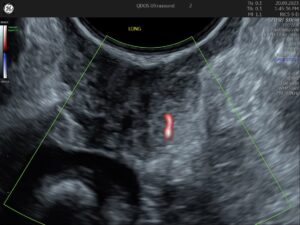

Abnormal bleeding sometimes can be linked to several conditions visible on an ultrasound, such as polyps, fibroids, abnormal thickening of the uterus lining, or unusual ovarian activity. At QDOS Ultrasound, we specialise in detailed gynaecological imaging to recognise the difference between these abnormal findings, as well as to recognise variations of normal.

Painful or heavy periods are common reasons for a gynaecology ultrasound. Conditions like fibroids, endometriosis, adenomyosis, uterine polyps, or abnormal thickening of the uterus lining may be responsible. Whilst endometriosis cannot be excluded by ultrasound, our team are specialists in looking for the recognisable ultrasound features of endometriosis.